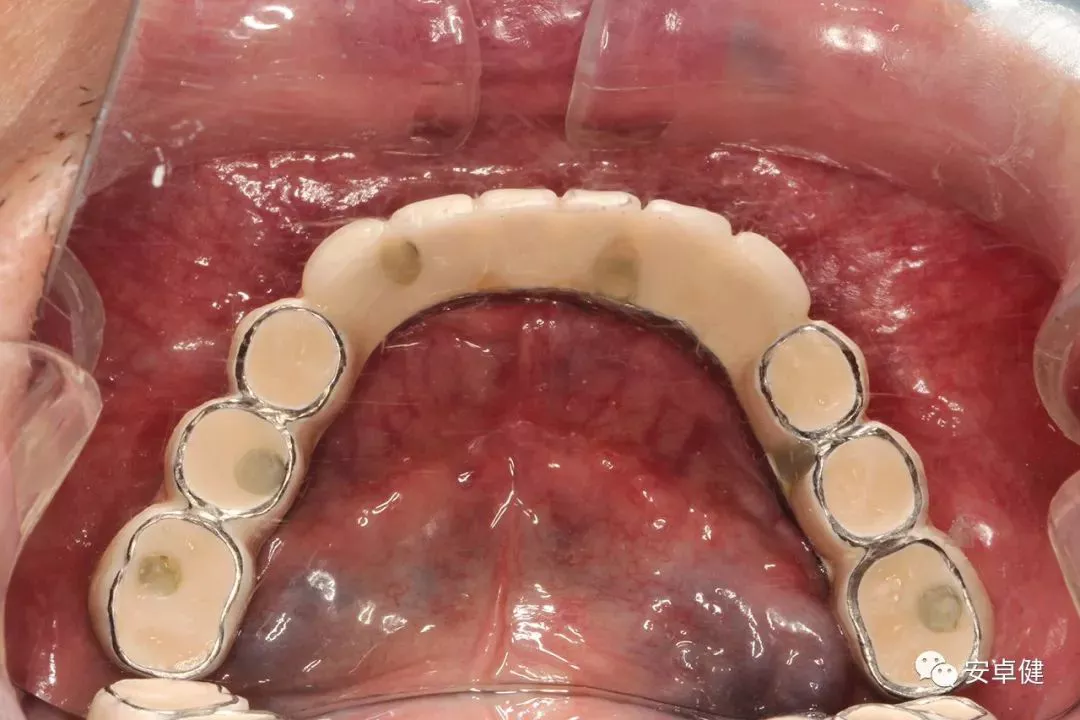

最终修复体合面照

最终修复体正面照

最终修复体正面咬合照

最终修复体侧面咬合照

最终修复复诊合面观

戴最终修复体合面观

▷ 永久修复

• 于口内试戴原厂纯钛切削一体式桥架,并检查前牙排蜡外形及后牙咬合关系;

• 聚合瓷烤塑制作最终修复体;

• 为减少牙面磨耗,于后牙区制作360度防裂纯钛金属带;

• 试戴满意后,二级螺丝加力至15N;

• 特氟龙封闭螺丝孔,光固化复合树脂封闭上方螺丝通道,完成最终固定式种植义齿修复;